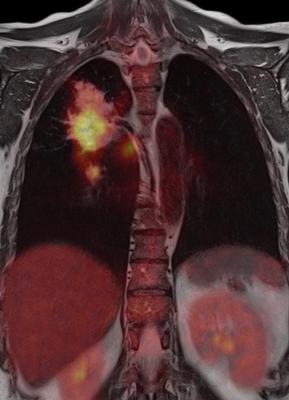

January 23, 2018 — Despite decades of clinical research establishing chemotherapy with thoracic radiation therapy as the standard-of-care for the initial management of non-metastatic small-cell lung cancer (SCLC), a large percentage of U.S. patients do not receive these treatments and in turn have lower overall survival, according to research from The University of Texas MD Anderson Cancer Center.

“For patients who received both chemotherapy and radiation, median survival was 18 months. Among the group of patients who received neither chemotherapy nor radiation, prognosis was dismal with a median survival of only 3-4 months,” explained senior author Stephen G. Chun, M.D., assistant professor of radiation oncology. “In order to improve access to care and address related disparities, it is critical to understand the barriers patients face when getting treated for lung cancer,” said Chun.

Patients who received chemotherapy and radiation had a median survival of 18.2 months. Patients who received either chemotherapy or radiation alone had a median survival of 10.5 and 8.3 months, respectively. Patients who received neither chemotherapy nor radiation therapy had a significantly worse median survival, 3.7 months, compared with all other treatment groups.